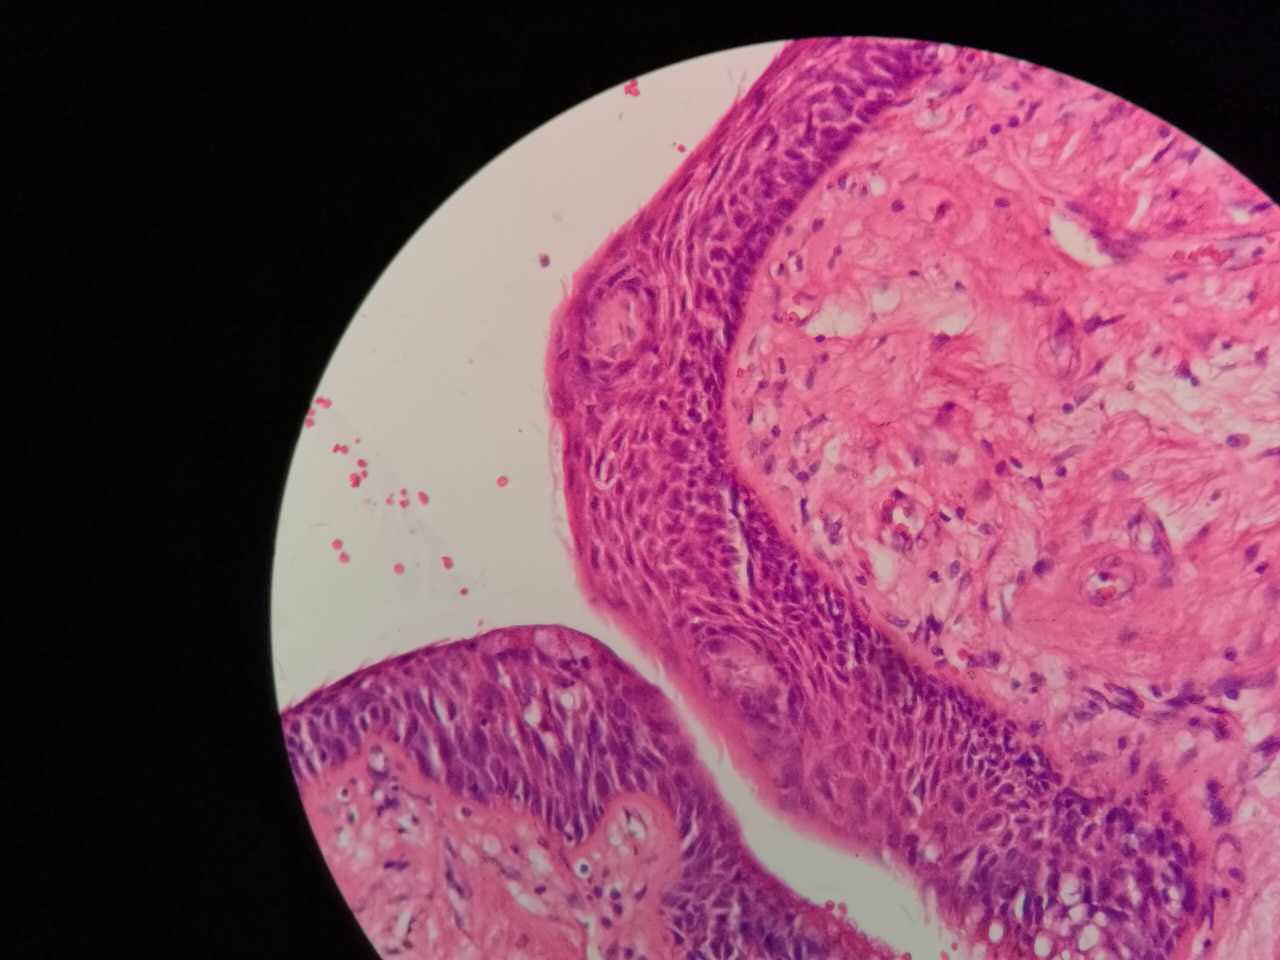

鳞癌生长,呈巢团状

巢团边界大多清楚

巢团可以很大,中央血供不足,就会坏死

中央红色的,有碎核

坏死也可以很大

较大的粉红区都是坏死,可以看出坏死是因为巢团大,中央坏死

下图是放大

鳞癌的核质比浸润性腺癌要紫兰一点儿

核仁也可以见到

但核仁不如浸润性腺癌明显

坏死会有许多团,有些只有一毫米大小,所以,建议增强扫描时候保留肿瘤区的薄层,以看到更多坏死区

左手边有一点鳞癌,右手边有正常肺泡组织,中间有坏死物,这是为什么呢?

坏死物质渗出。

并且可以有吞噬,坏死物里常有血液成分

肿瘤周围不应是缺血,坏死一般在巢团内

非角化型鳞癌

细胞胖胖的,核大而淡染

也是巢团状,也容易坏死

与实体型腺癌有时难区分,做免疫组化鉴别

左边坏死挺多

红染的,核没了

特征不明显

这是一般的鳞癌,坏死大

一侧常有突起,也就是壁结节。

壁结节不必等到空洞形成才判断,有坏死区就可以在增强片上判断有无壁结节

这个中央那块也算是小型的壁结节,肿瘤组织突入坏死区。或者说,这块肿瘤组织没坏死。